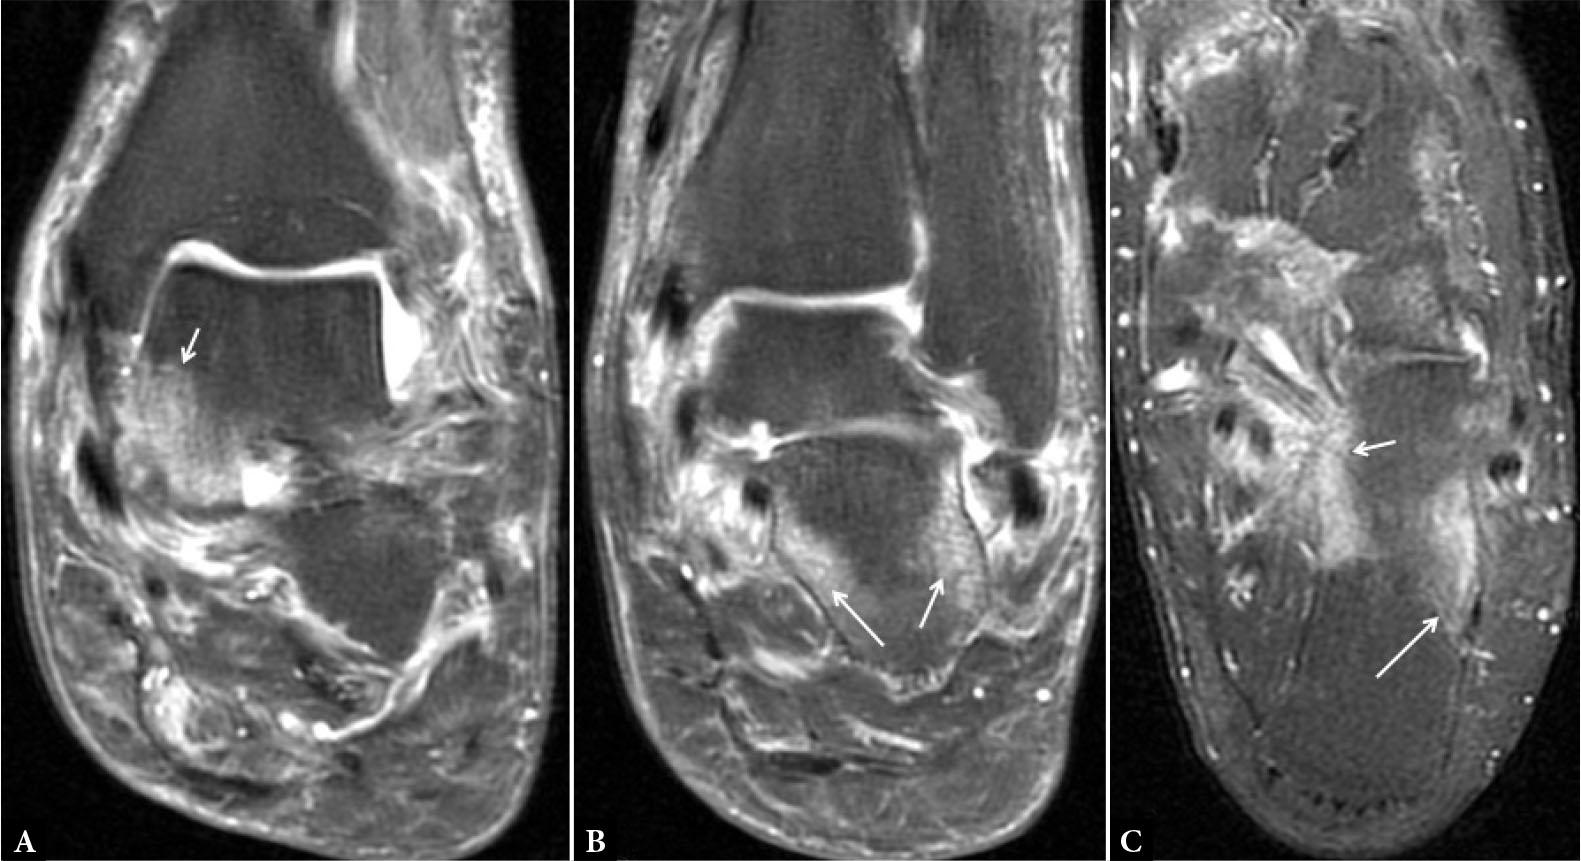

Fig. 19.

Enthesitis. MR proton density fat-suppressed coronal (A and B) and axial images of the ankle show extensive marrow edema (hyperintensity) at the attachment sites of ligaments (small arrows in A and C); retinaculum (arrows in B) and fascia (long arrow in C)